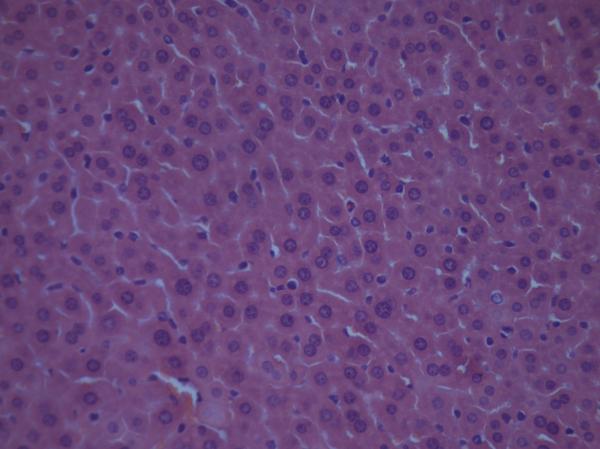

Çó¸ßÈ˰ïæ¿´Ð¡Êó¸ÎÔàÇÐÆ¬